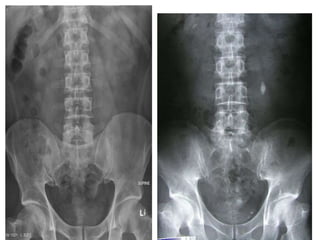

• 8.

• 11.